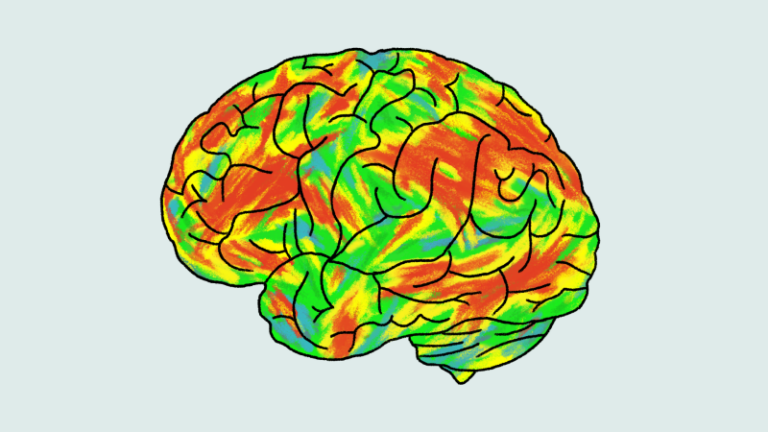

What experts say about taking psilocybin as an alternative treatment for depression

The matchup: Two doses of psilocybin, the active ingredient in “magic mushrooms,” against a six-week course of the popular antidepressant…

The matchup: Two doses of psilocybin, the active ingredient in “magic mushrooms,” against a six-week course of the popular antidepressant…